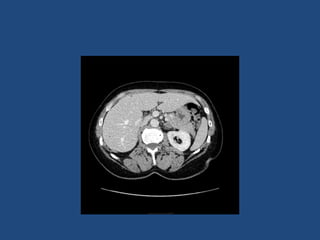

Imaging

• CT better at eliminating malignancy

(dedicated CT looking at Hounsfield units (HU)

and washout characteristics)

– <10HU = benign (sens 71%, spec 100%)

• MRI may characterise phaeos better

• FDG-PET good for phaeos and cancer

• FNA – consider if cancer history and >10HU on CT

after exclusion of phaeo

Imaging - size

• >4cm 90% sensitivity carcinomas

24% specificity (ie only 24% cancer)

• >6cm 25% chance of it being carcinoma

• <2cm + hypodense then unlikely to grow

• If change in size >1cm over 6 months consider

resection

Imaging • CT betterat eliminating malignancy (dedicated CT looking at Hounsfield units (HU) and washout characteristics) – <10HU = benign (sens 71%, spec 100%) • MRI may characterise phaeos better • FDG-PET good for phaeos and cancer • FNA – consider if cancer history and >10HU on CT after exclusion of phaeo

Imaging - size •>4cm 90% sensitivity carcinomas 24% specificity (ie only 24% cancer) • >6cm 25% chance of it being carcinoma • <2cm + hypodense then unlikely to grow • If change in size >1cm over 6 months consider resection • Guidelines suggest: – NIH: 2 CTs 6M apart – Young et al + UptoDate: 0,6,12,24m – BES: Repeat image – increase in size of 0.8cm over 6-12M consider surgery